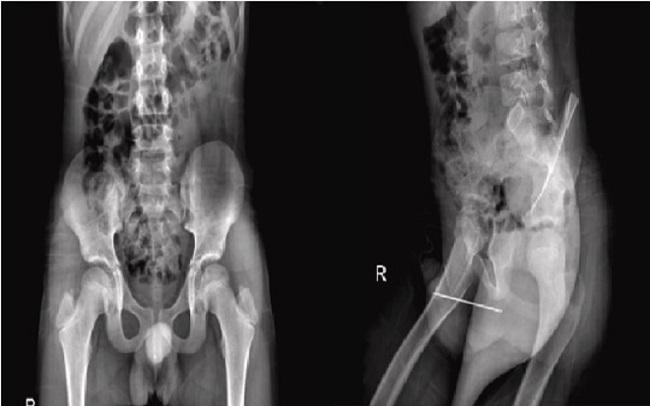

यूरोलॉजी केस रिपोर्ट्स के जर्नल में प्रकाशित यह घटना बेहद दुर्लभ है. एक्स-रे रिपोर्ट से पता चलता है कि 87mm की नुकीली सुई अंदर ऐसी स्थिति में थी जिसे सामान्य तरीकों से बाहर निकाल पाना असंभव था. इसलिए डॉक्टर ने पहले उसे इफेक्टेड एरिया में एनेस्थेटिक इंजेक्शन दिया और फिर सुई को बाहर निकालने का प्रयास शुरू किया गया. रिपोर्ट के मुताबिक, डॉक्टर्स ने सुई के चौड़े सिरे को दबाकर नुकीले हिस्से को स्किन में प्रवेश कराया और फिर उसे बाहर निकाला.